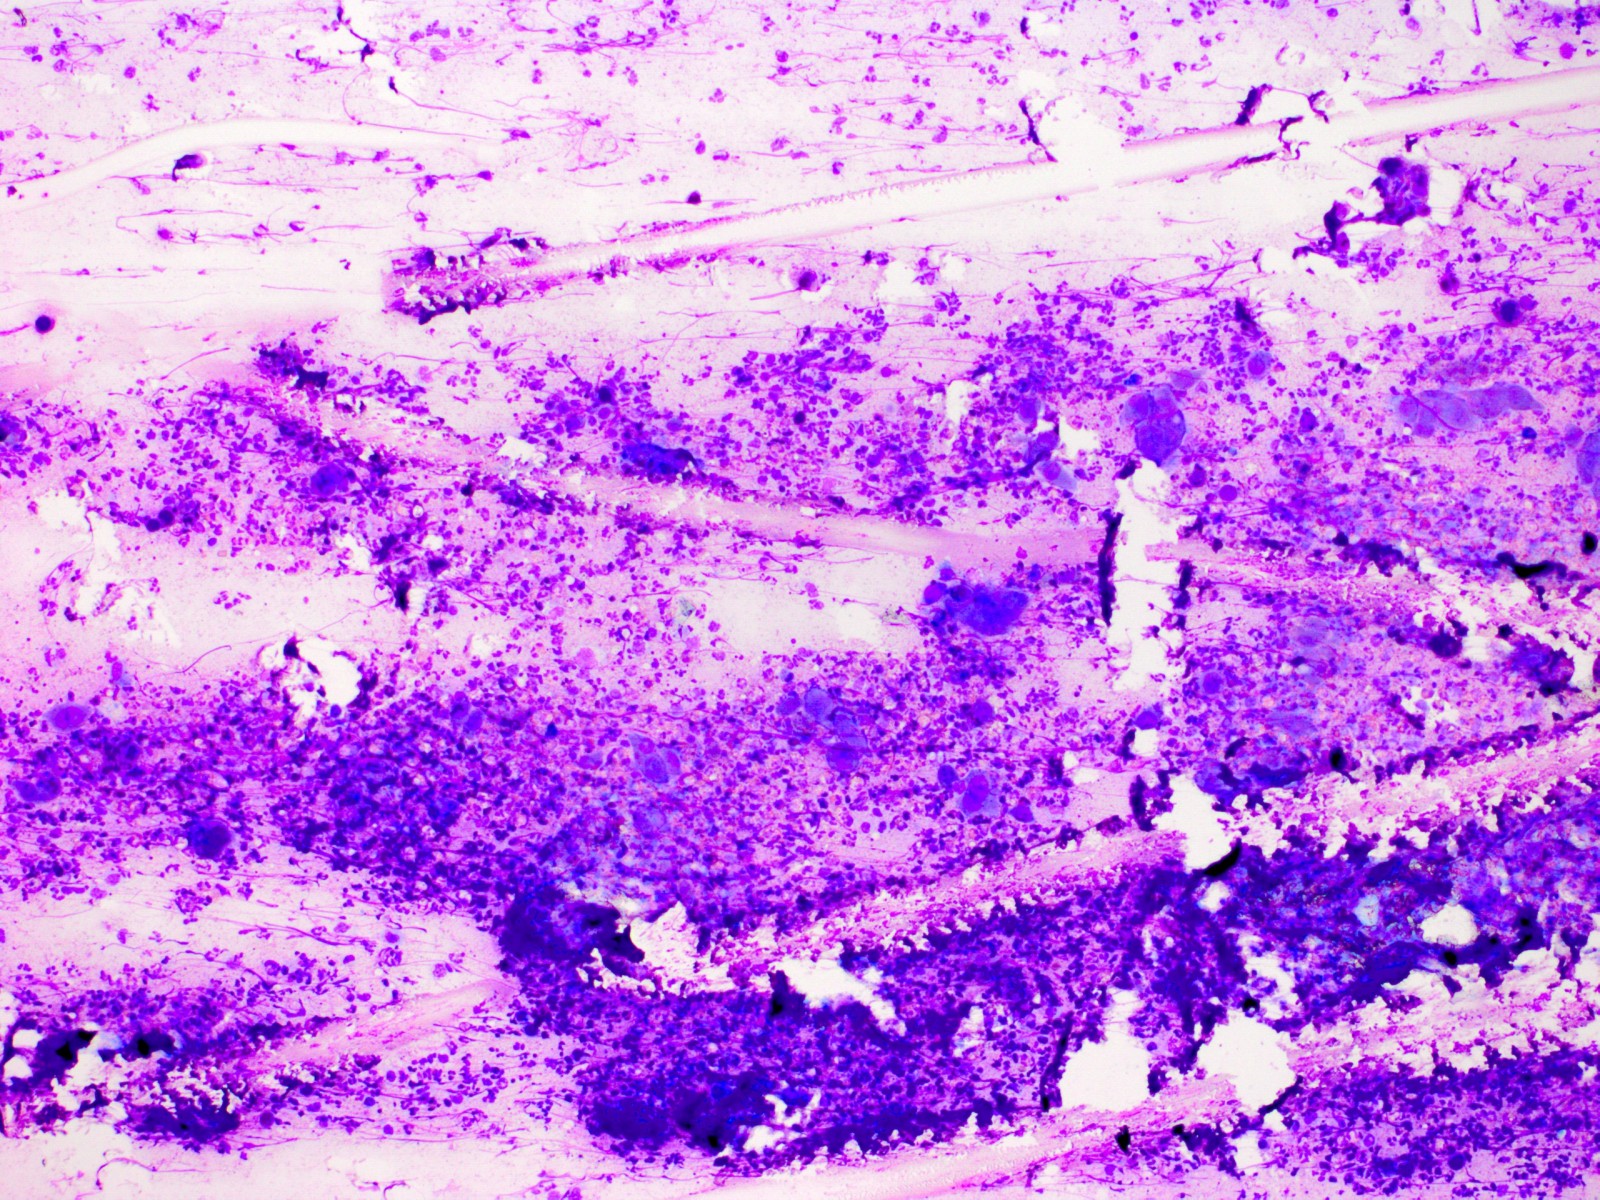

De Tzanck reuscellen hebben in het Diff-Quick preparaat een lichtblauw (basofiel)

cytoplasma en een homogene donkerblauwe of paarse kern (hyperchromatisch, sterk

aankleurend), en zijn zeer groot, veel groter dan een granulocyt. Het zijn geen

macrofagen of Langhanse reuscellen, het zijn conglomeraten van grote epitheliale

cellen (keratinocyten). Er kunnen in het preparaat ook losse van deze grote

hyperchromatische epitheelcellen liggen, maar diagnostisch is het vinden van

een klompje waarbij het cytoplasma samengesmolten is en de kernen tegen elkaar

aanliggen. Losliggende grote afgeronde epitheelcellen (Tzanck cells) kunnen

![Tzanck test met multinucleate giant cells (click on photo to enlarge) [source: www.huidziekten.nl] Tzanck test met multinucleate giant cells](../../../images/soa/Tzanck-test-4z.jpg) |

Tzanck

test |